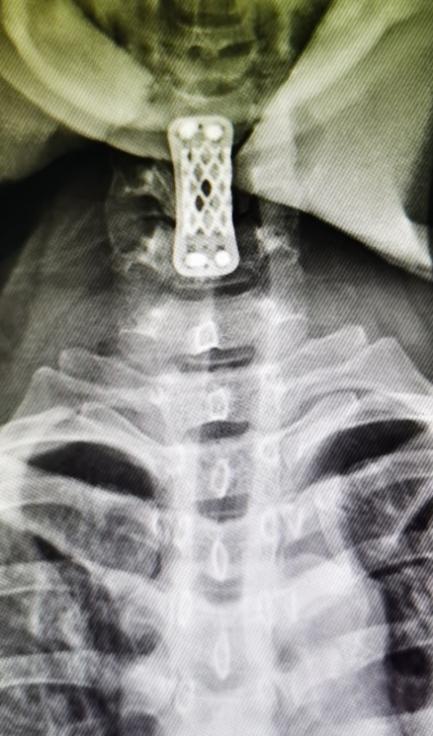

该患者系“右上肢麻木伴左下肢疼痛半年”入院,术前颈椎MR提示C5-6水平脊髓前方囊性占位(图1),囊肿的基底部位于前正中裂至中央管内(图2)。经科室讨论,采用显微镜下颈前经椎体入路脊髓内肠源性囊肿切除术。术后第四天复查磁共振见囊肿全切,无残留(图3),术后颈椎X线片显示内固定位置良好,颈椎曲度理想(图4.5)。术后患者恢复良好,术后第四天患者自己可以下床行走,四肢肌力正常(图6),右上肢麻木稍减退,左下肢疼痛感消失。

图4:颈椎侧位片

图5:颈椎正位片